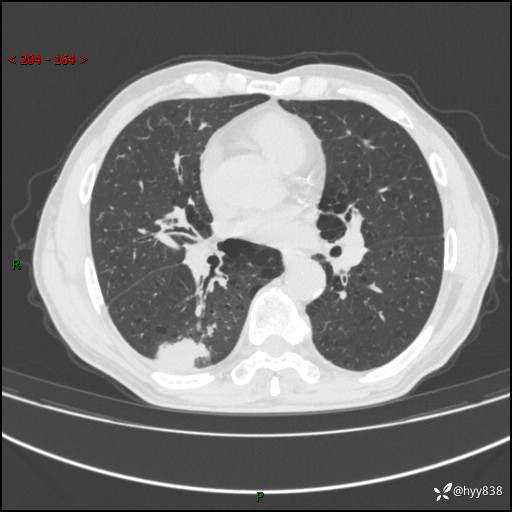

老年男性,发现右下肺结节3天。结节+卫星灶,似曾相识---结果公布~

简要病史:患者3天前于我院常规体检时行胸部CT提示“右下肺结节35mm*24mm”,自觉无发热、咳嗽、咳痰,无胸痛、咯血、气促加重,无声嘶、吞咽困难,无乏力、盗汗、体重减轻等不适。为求进一步诊治,入我院求诊,门诊以“右下肺结节待查”收入我科。患者3天前于我院常规体检时行胸部CT提示“右下肺结节35mm*24mm”,自觉无发热、咳嗽、咳痰,无胸痛、咯血、气促加重,无声嘶、吞咽困难,无乏力、盗汗、体重减轻等不适。为求进一步诊治,入我院求诊,门诊以“右下肺结节待查”收入我科。 起病以来,患者精神、食欲、睡眠可,体力稍差,大小便正常,体重无明显变化。

辅助检查:CT

胸部CT平扫

增强